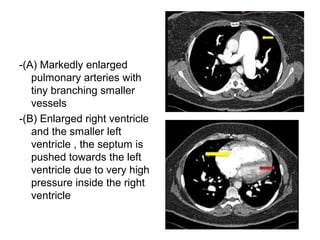

-(A) Markedly enlarged

pulmonary arteries with

tiny branching smaller

vessels

-(B) Enlarged right ventricle

and the smaller left

ventricle , the septum is

pushed towards the left

ventricle due to very high

pressure inside the right

ventricle